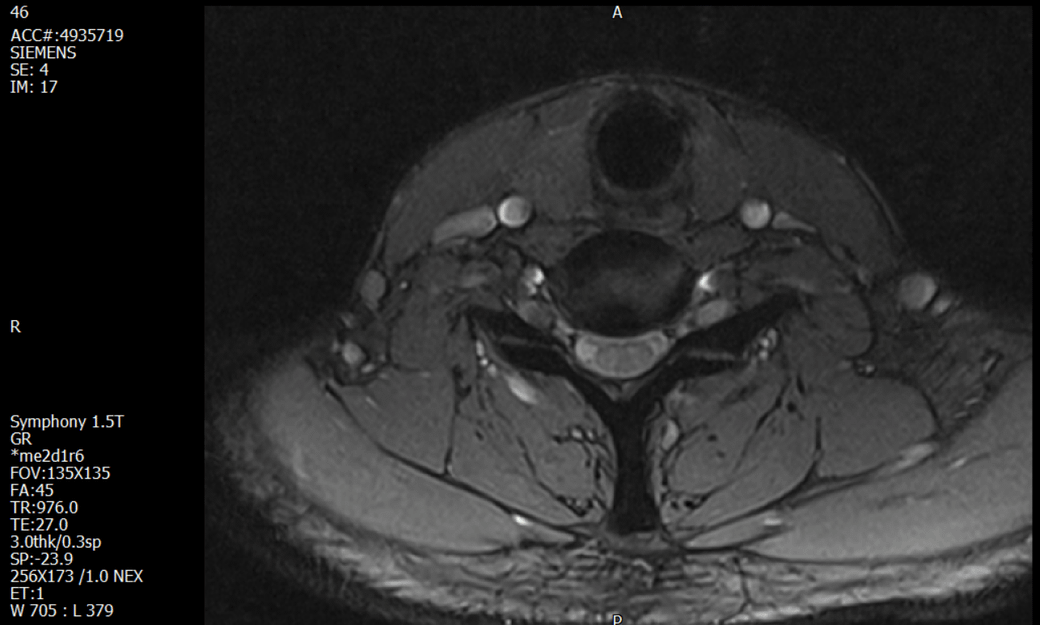

경추 요추 디스크 MRI판독 부탁드립니다.

- 3개월전 좌측 상지 저림(힘빠짐) 발생. 이틀뒤 에 좌측 하지 저림(힘빠짐) 발생.

(힘이 축처지는 느낌이라서 힘빠짐이라고 하지만, 실제 근력 문제, 감각이상, 활동 문제 없음)

-11월, 증상발생 직후 잠실소재 척추전문병원 MRI 요추경추 촬영 후 신경외과 박사 진료, 허리는 매우 건강, 경추는 퇴행성 진행되고 있지만 디스크라고 보기 어려움. 신경막만 살짝 건드리는 정도고 이 정도로 힘빠짐이나 저림이 오지 않고 원인은 다른 곳에 있을 가능성.

-12월, 분당서울대병원 재활의학과 진료, MRI 영상보고 딱히 다른 말은 없었음. 근전도 검사해보자 해서 신경전도, 근전도 검사 진행, 검사결과 이상없었고, 신경쪽 문제는 아예 배제해도 될것이라고 함. 정신쪽에 기인한 문제일 가능성 제시.

-올해 1월, 국립암센터 재활의학과 진료, 병명을 찾기가 쉽지 않을 것

-올해 1월, 분당서울대병원 신경과 진료, MRI영상보더니 디스크가 있고 저림과 힘빠짐이 이에 기인했을 가능성이 충분히 있다고함. (경추만 말한것인지 요추도 포함인지 모르겠으나 디스크 시술 방안을 제시함) , 팔다리가 우연이 동시에 저림이 올수 있는지에 대해서 물었더니 이틀 상간으로 발생했기 때문에 동시라고 보기 어렵다고함...

1. MRI 상 , 경추와 요추에 디스크가 있나요? 있다면 좌측 팔과 다리에 저림 및 힘빠짐을 줄 정도인가요?

• 1. MRI 사진을 보았을 때 디스크를 의심해볼 수 있는 소견이 살짝살짝 보이긴 합니다만, 상하지의 저림 및 힘빠짐을 유발할 정도인지는 솔직히 회의적입니다.

2. 영상의 퀄리티는 나쁘지 않아 보입니다. 굳이 재촬영을 하실 필요는 없어 보입니다.

3. 개인적으로는 디스크로 인한 증상이 아닐 것으로 보나, 만약 디스크가 맞다면 우연하게 목과 허리 디스크 발병이 이틀 간격을 두고 나타났을 가능성을 생각해야 하는데, 현실적으로 그 가능성이 높지 않습니다.

4. 말씀하신 것처럼 특히 요추부 MRI는 디스크를 찾기 어렵습니다.

상기 MRI 소견으로는 심한 증상을 보일 정도는 아니며 디스크의 가능성은 적어보입니다.